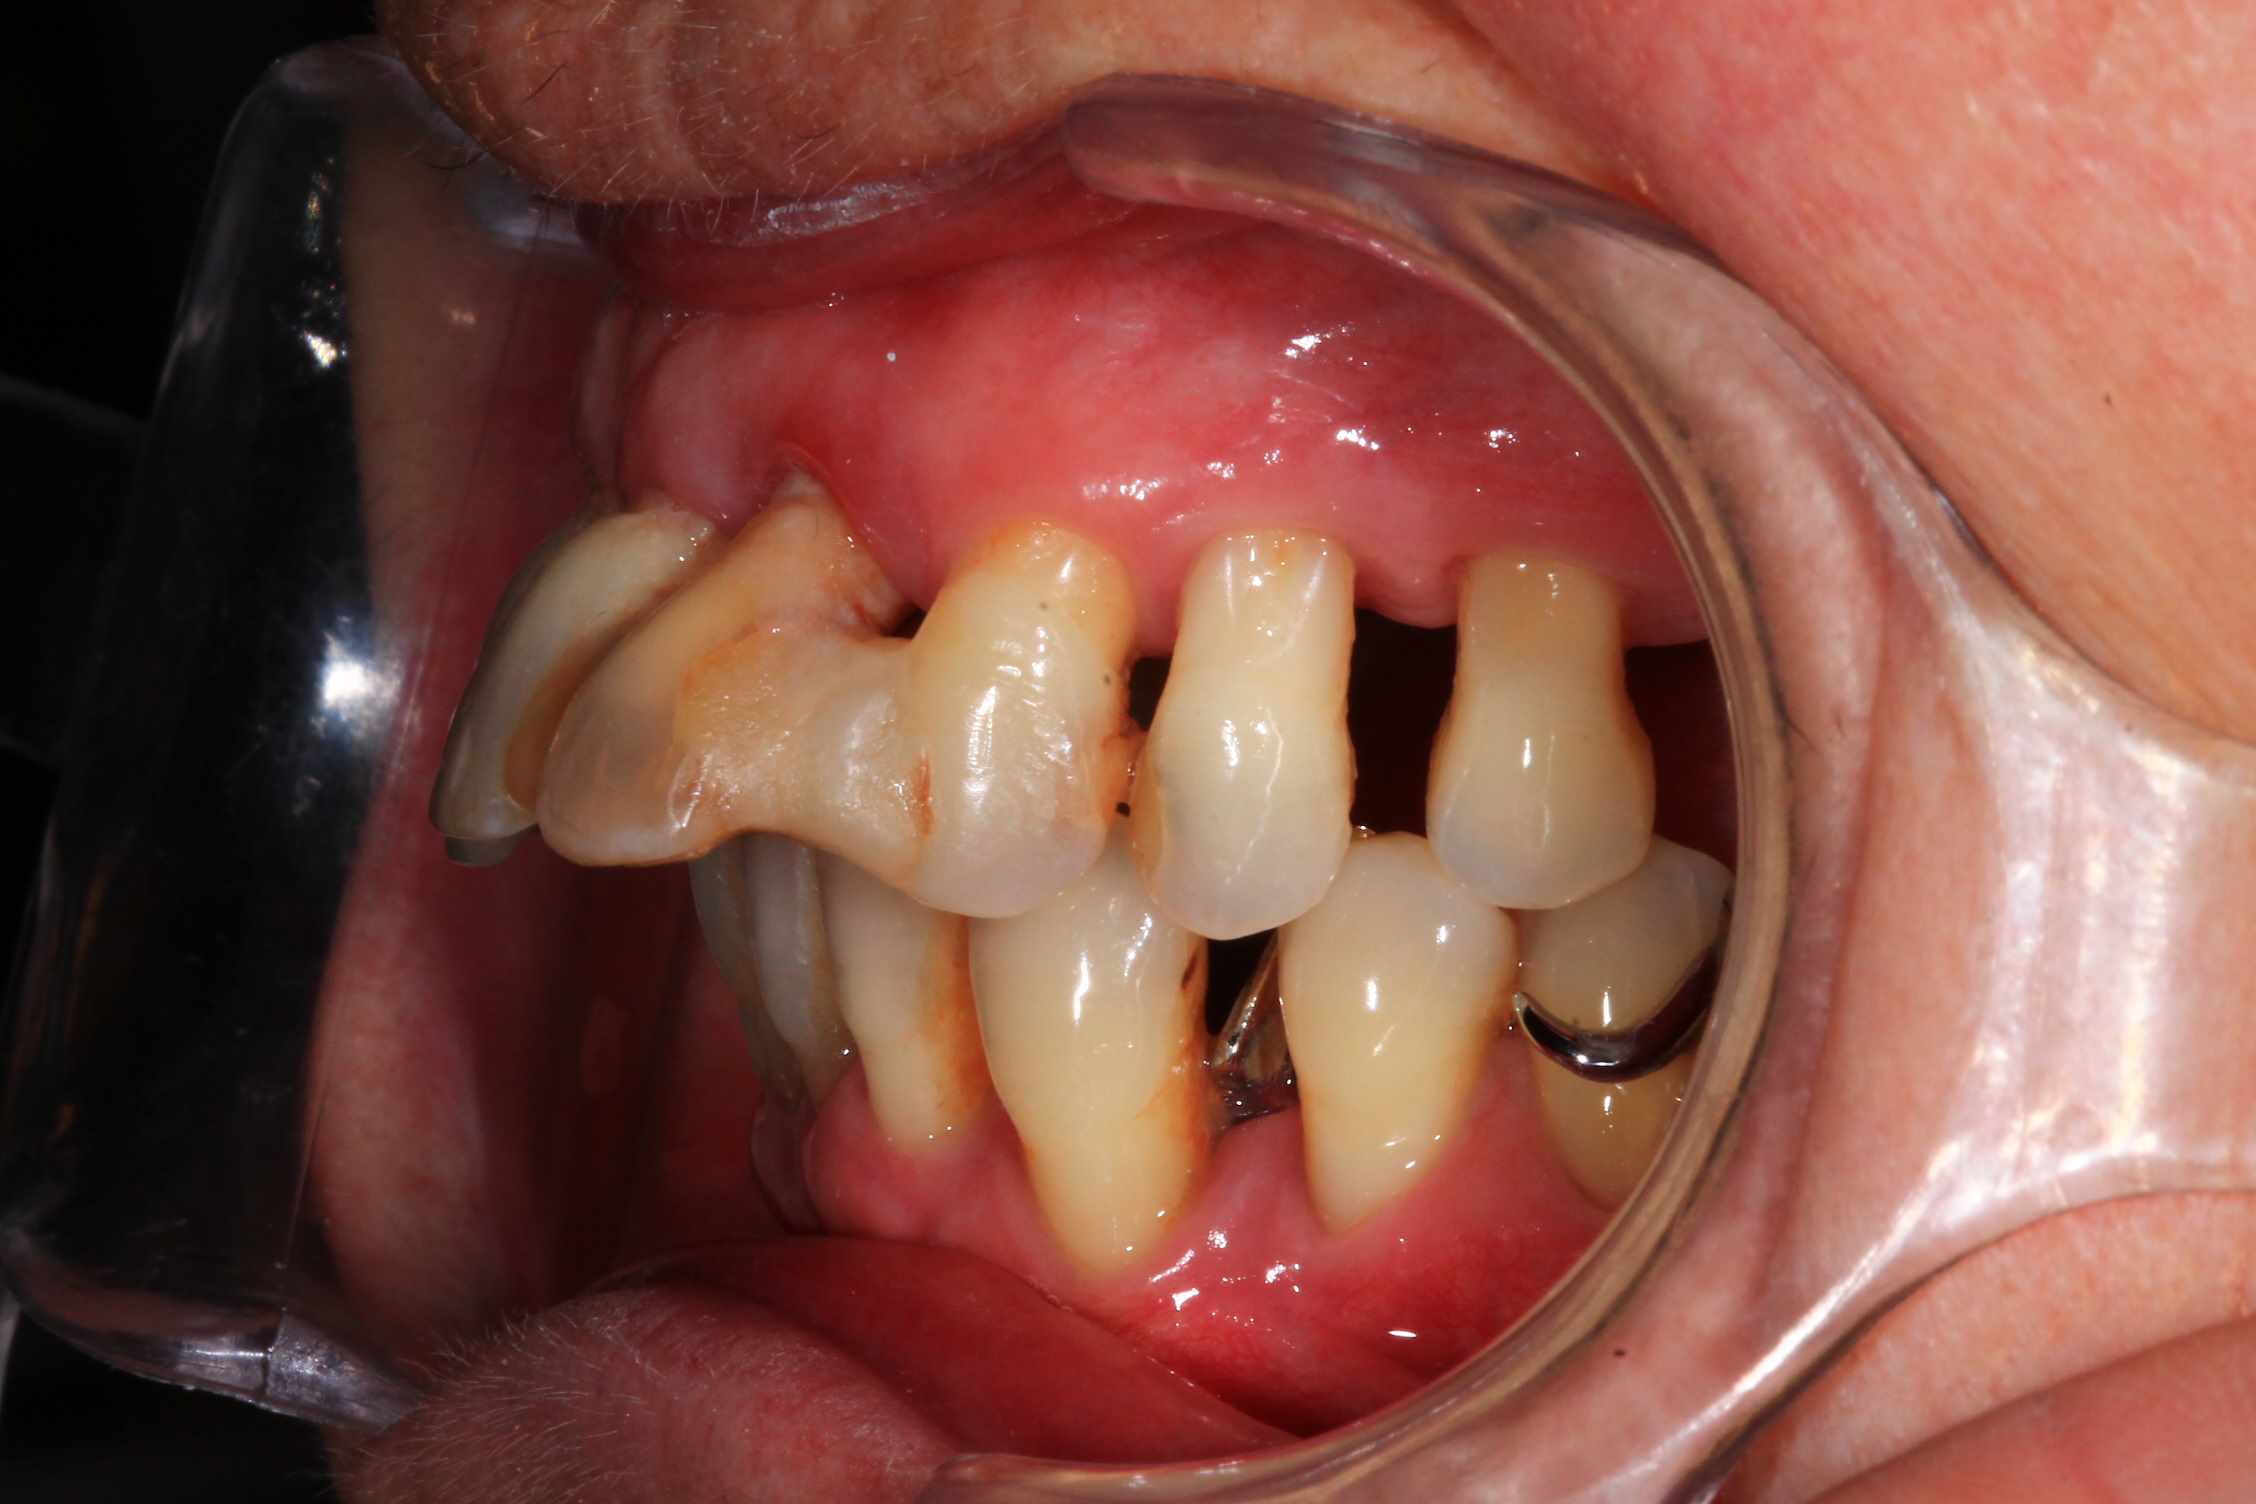

Cas 1 : patient ayant une 23 fracturée, avec 11 21 22 en mobilité terminale.

Planification des extractions, pose de 3 implants et mise en esthetique instantanée.

la seule chose qui m'interpelle, c'est de voir une bouche avec autant de travail (9 implants dont 6 anciens) et aussi peut de soins d'hygiène,...

:) . effectivement terrain paro chronique, déjà traité il y a quelques année a paris. Plus ou moins stabilisé, pas de saignement, un peu de tartre en bas. des mobilités importantes sur les incisives antérieures qui, avec la facture de la 23 ont emporté ma décision. Solution alternative : stellite ? dans un an, tu extrais les dents support de crohet. Bridge ? cela me semble plutôt casse gueule.

Donc, implant , sur un terrain qui n'est pas idéal, certes, mais c'est souvent le cas.